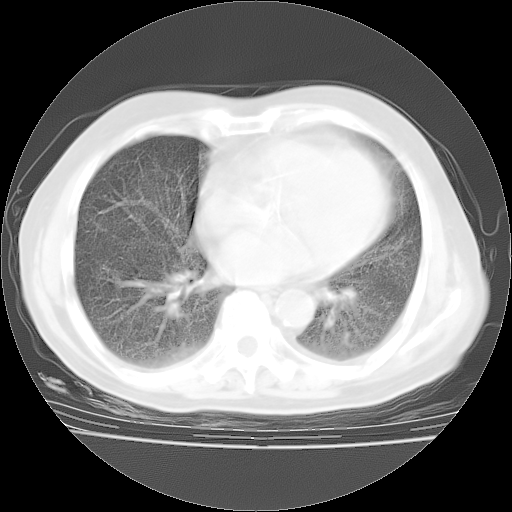

4月14日肺部CT

4月28日肺部CT——再次出现类似去年5月9日——透光度降低,(影像科认为)“间质性”改变。